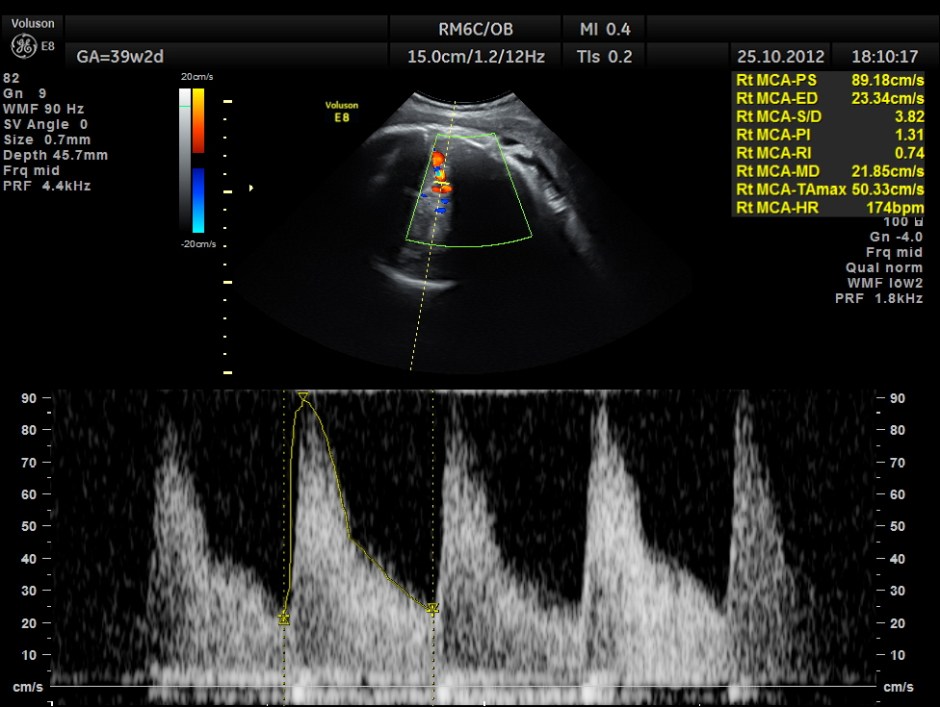

MIDDLE CEREBRAL ARTERY SHOWS HIGH PEAK SYSTOLIC VELOCITY OF 89.1 CMS/S ; M.O.M. WAS AROUND 1.59 SUGGESTIVE OF SEVERE FETAL ANEMIA